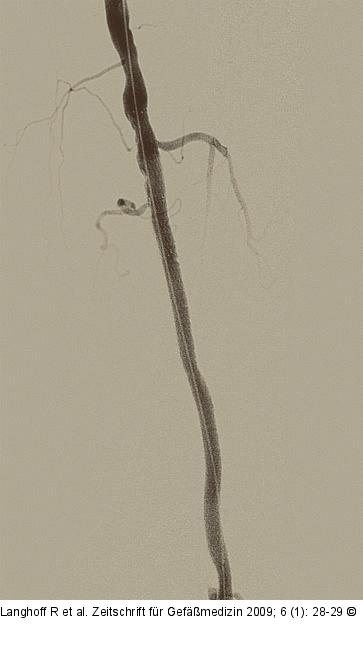

Abbildung 4: PTE Sicherung des PTA-Ergebnisses durch Stentimplantation. |

Sicherung des PTA-Ergebnisses durch Stentimplantation. |